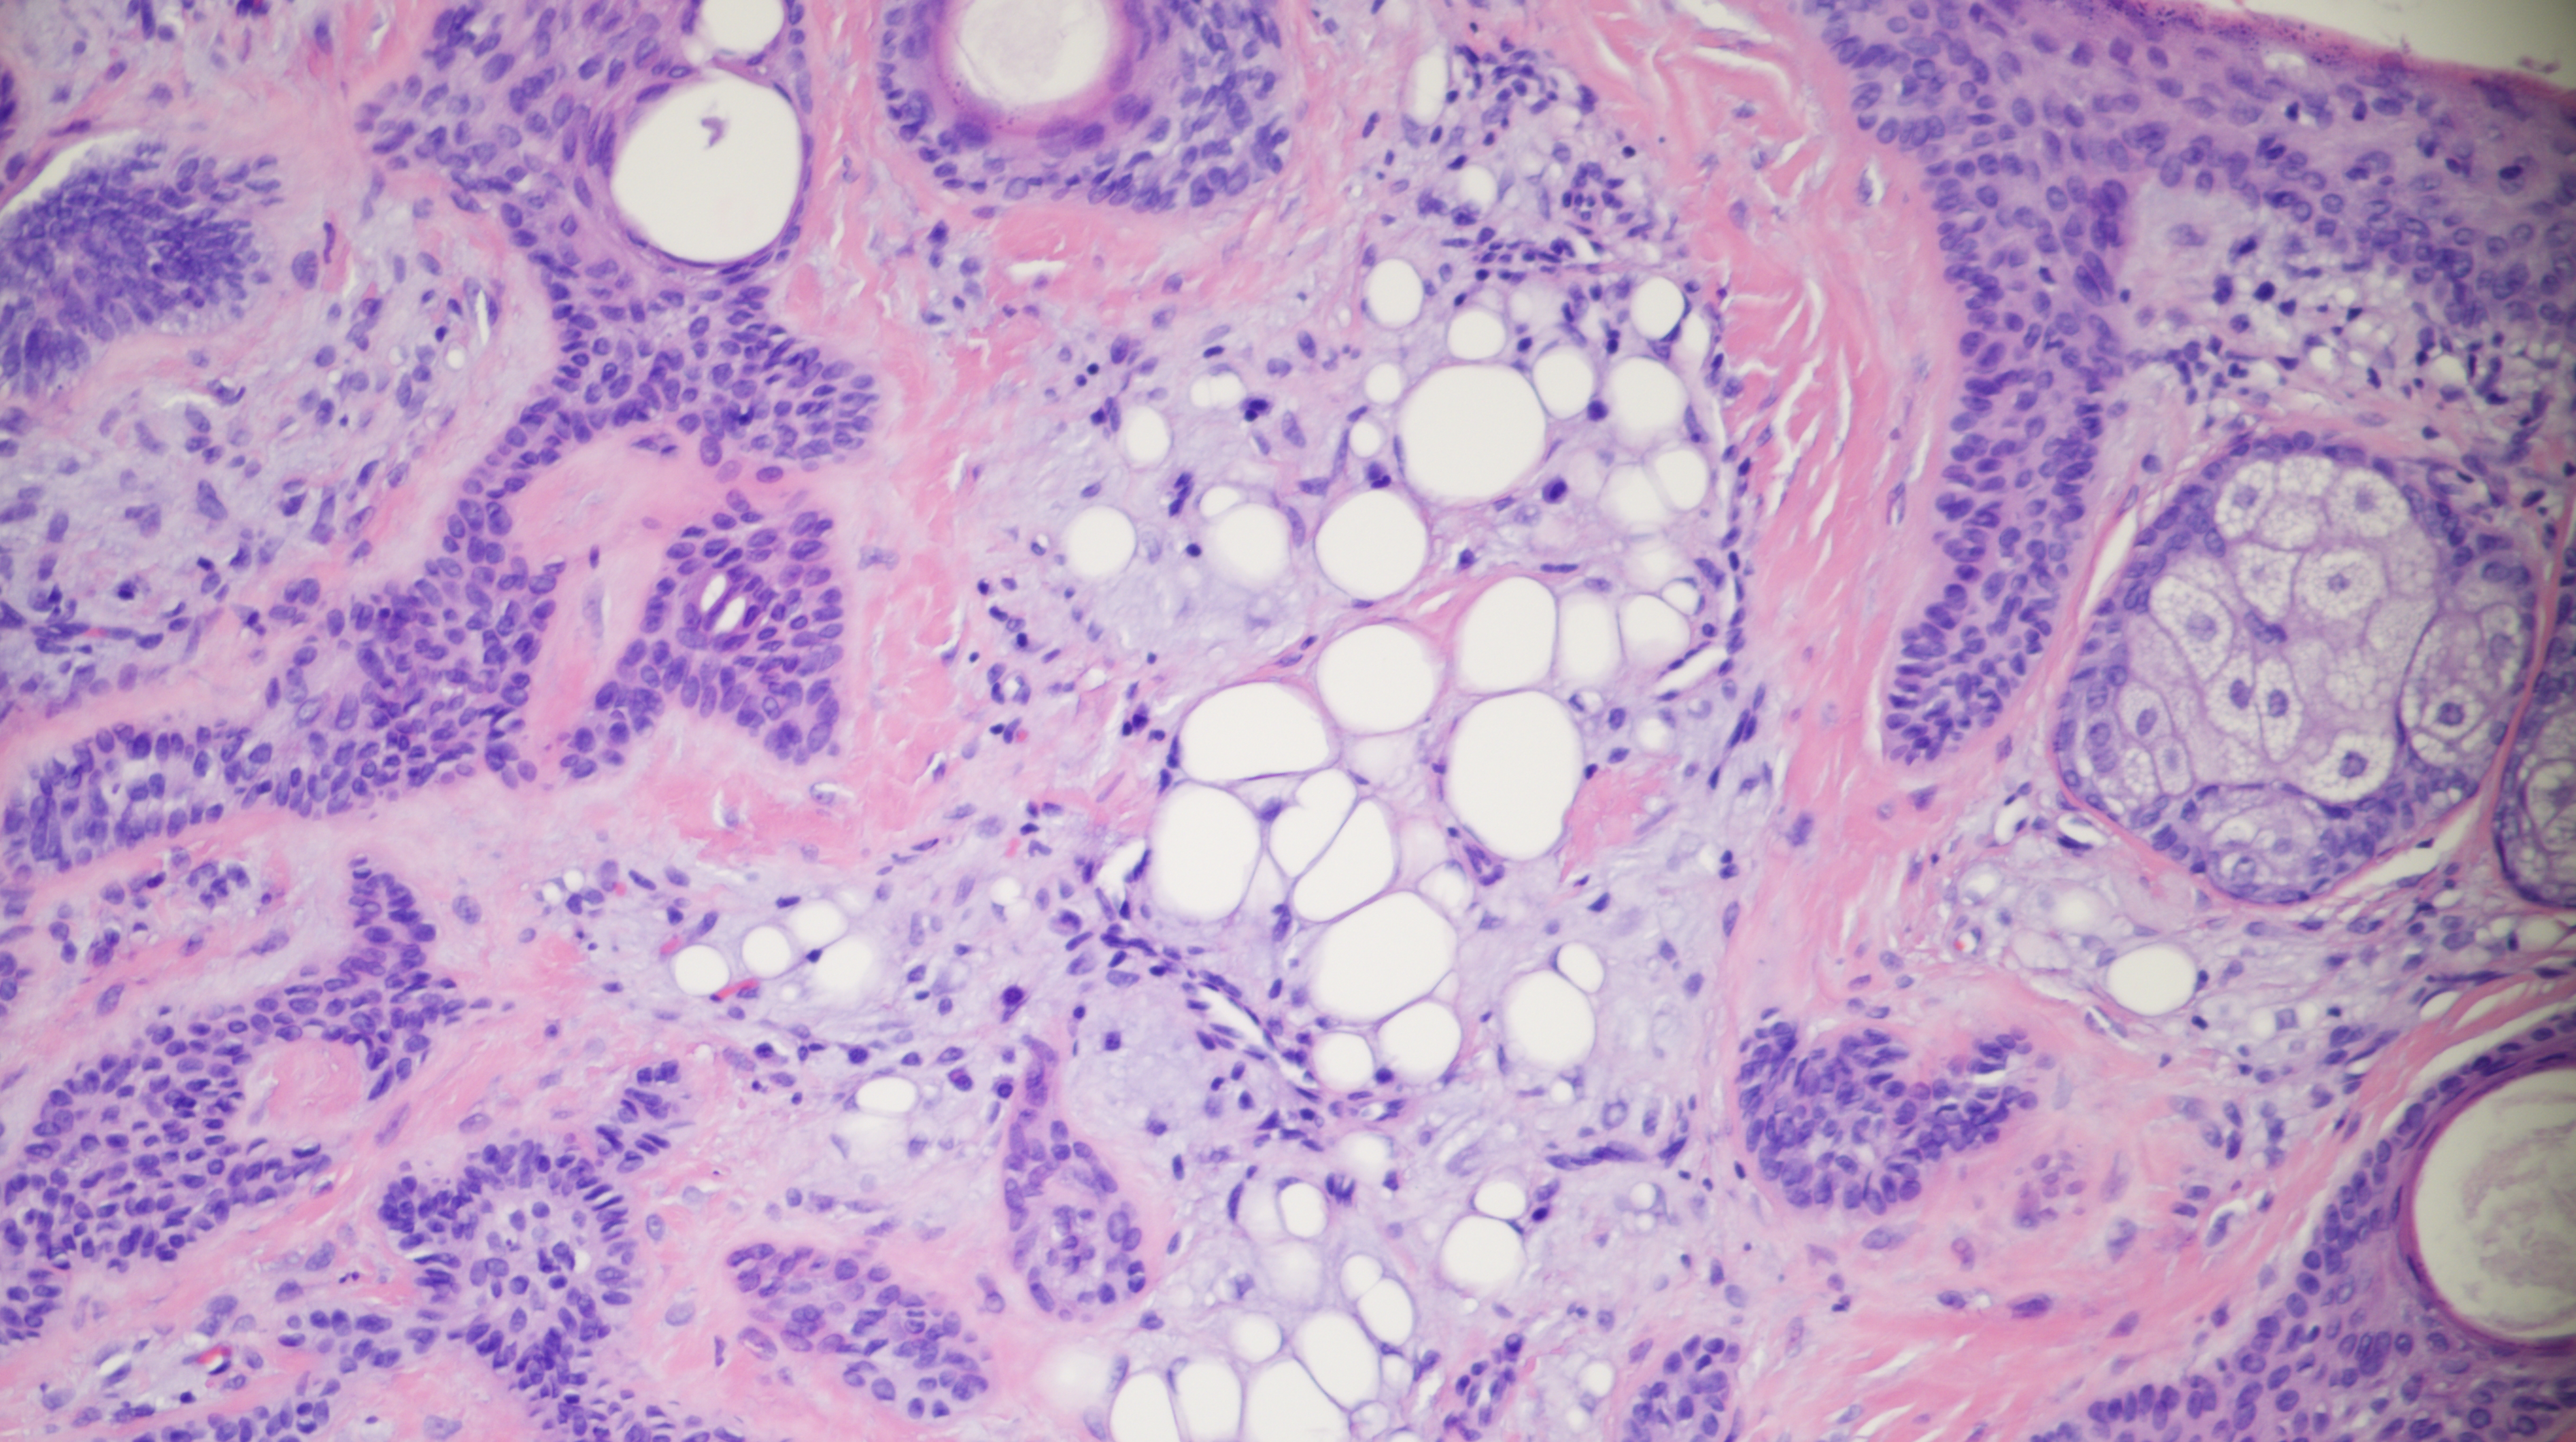

60-year-old man with an upper lip nodule.